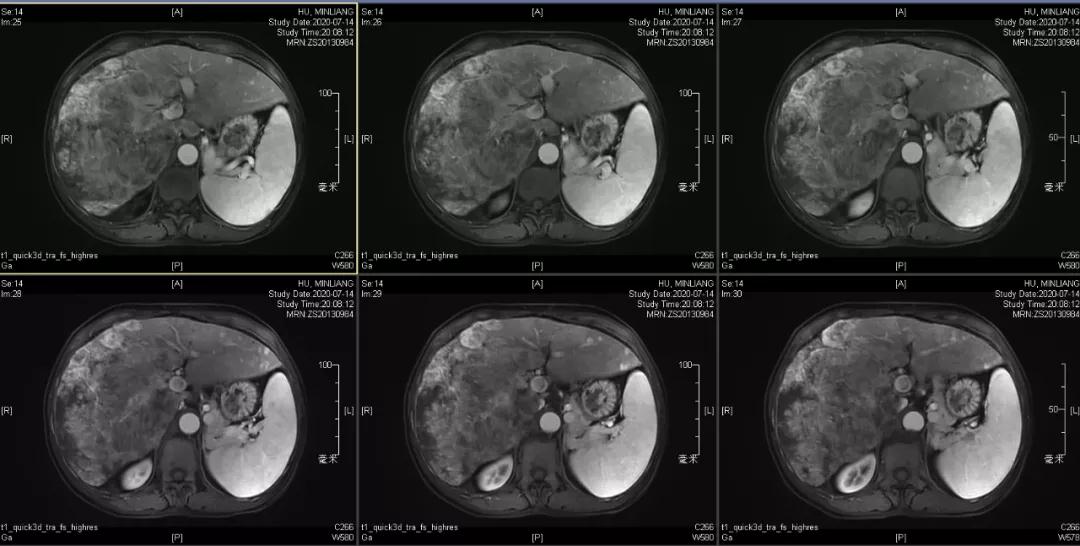

肝脏弹性超声:12kPa。腹部MRI平扫+增强:肝巨块结节性HCC(最大径18.4cm)伴肝内多发转移(最大径3.5cm),肝右静脉广泛癌栓形成;肝硬化伴门脉高压、脾大、少量腹水;肝囊肿;双肺多发转移。胸部CT平扫:两肺多发转移,两肺气肿伴肺大泡,两肺散在慢性炎症,右侧少量胸水。

Δ肝脏MRI,最大肿瘤18.4cm